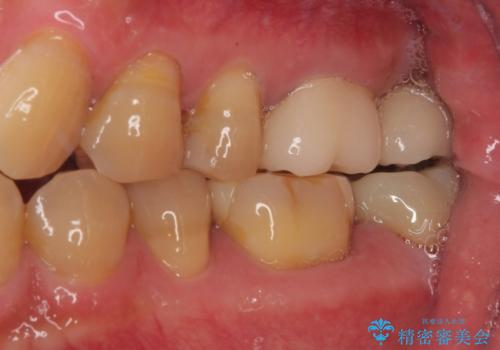

欠損した奥歯 インプラントによる補綴治療

- 破損したクラウンと、奥歯の欠損を気にして来院された患者様です。

奥歯の欠損部はインプラントによる補綴治療を、手前の破損したクラウンは作り替えをご希望でした。

しかしながら、レントゲンやCT画像から、手前の破損したクラウンの根尖部に大きな病変が認められ、インプラント埋入部にまで病変が及んでいることから、まずは手前の根管治療を行い、病変の正体を確認した後にインプラント埋入を行うこととしました。

口があまり開かず、インプラントの埋入角度がやや斜めとなりましたが、機能的には全く問題なく治療を終えることができました。